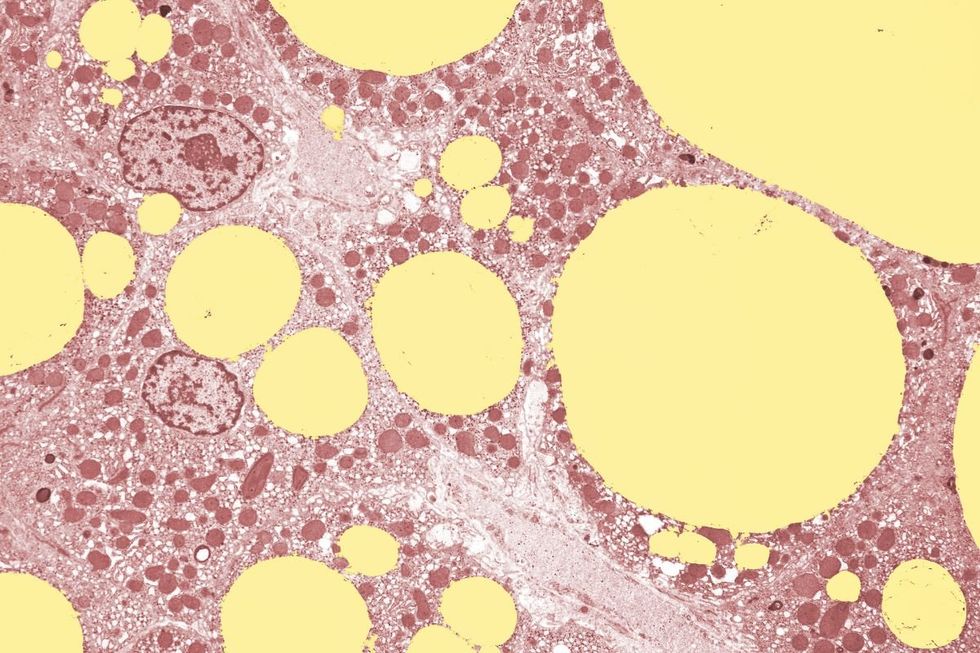

Bubble tea consumption could have long-term consequences for the liver

|GETTY

The long-term consequences include heightened risks of type 2 diabetes, obesity and fatty liver disease.